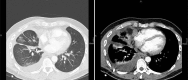

Malignant pleural mesothelioma is a rare malignant disease that in the majority of cases is associated with asbestos exposure. The incidence in Europe is about 20 per million inhabitants and it is increasing worldwide. Initial symptoms are shortness of breath, pleural effusion, cough, and chest pain. The typical growth pattern is along the pleural surface; however, infiltration of the lung and/or mediastinal and chest wall structures can occur in a more advanced stage. Ultimately, distant metastases outside the chest can result. Several histological subtypes of pleural mesothelioma exist, which must be differentiated from either benign diseases or metastases in the pleural space by other tumor entities. This differential diagnosis can be very difficult and a large panel of immunohistochemical markers is required to establish the exact diagnosis. The standard procedure for confirming the disease and obtaining sufficient tissue for the diagnosis is videothoracoscopy. Full thickness biopsies are required, while transthoracic needle puncture of pleural fluid or tissue is considered to be insufficient for a cytological diagnosis. Complete and detailed staging is mandatory for categorization of the disease as well as for therapeutic decision making.